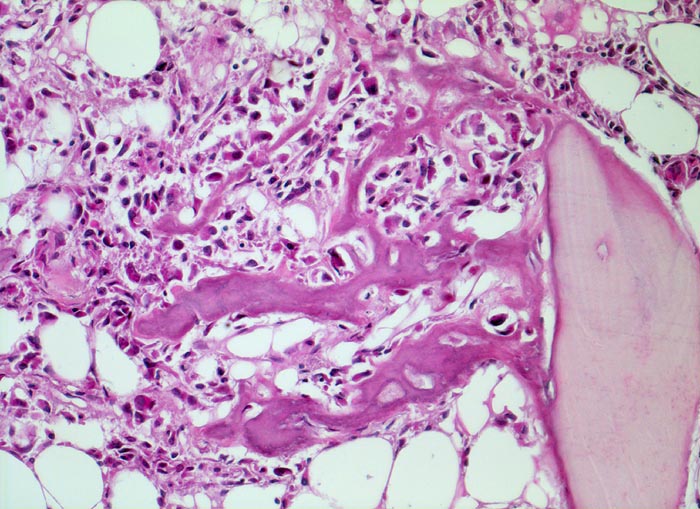

Morphologische Merkmale:

• Tibiametaphyse mit angrenzendem Weichteilgewebe.

• Das Sarkom infiltriert diffus den spongiösen Knochen der Diaphyse und hat präexistente Knochenbälkchen verdrängt.

• Der Tumor hat die Korticalis destruiert und infiltriert die angrenzende Skelettmuskulatur.

• Der Tumor besteht aus neugebildetem bereits verkalktem Knochen oder einem Netzwerk von primitiven Osteoidtrabekeln. Entlang oder innerhalb der Osteoidtrabekel lokalisierte polymorphe Tumorzellen mit ausgeprägten Kernatypien und zahlreichen Mitosen. Leicht verwaschene Kernstrukturen als Folge der Gewebsentkalkung.